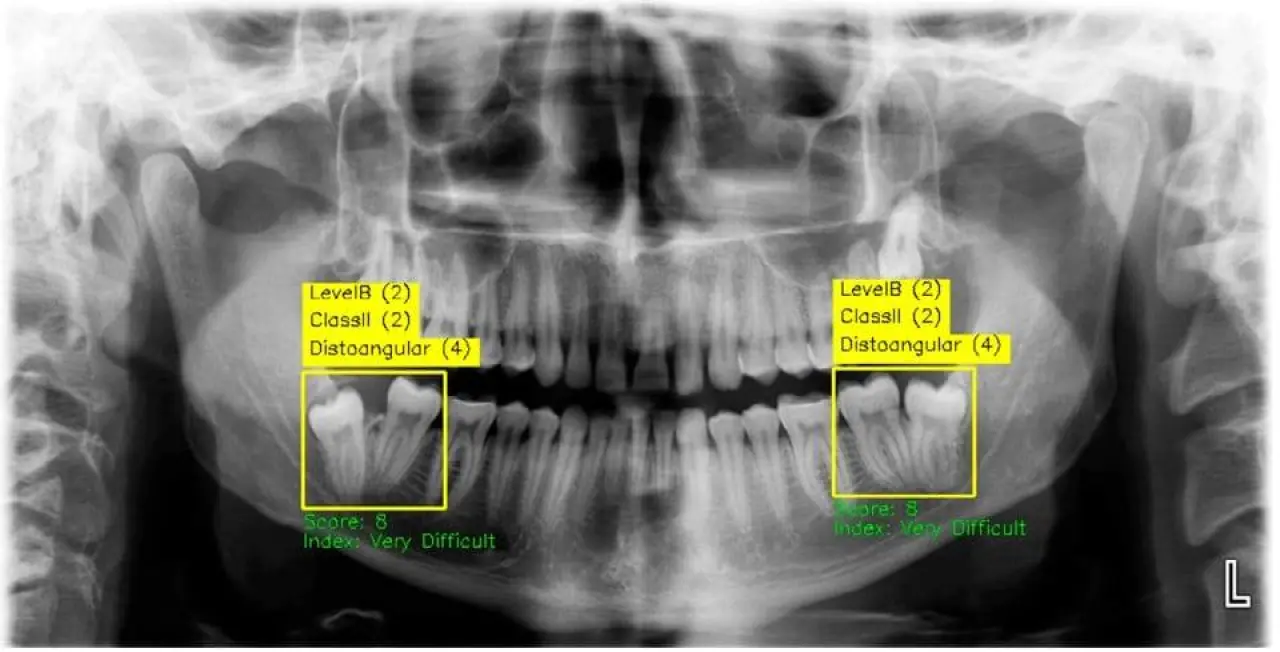

Üniversitenin Diş Hekimliği Fakültesi Öğretim Üyesi Prof. Dr. Melek Taşsöker Bulut, ağız ve çene radyolojisinde yapay zekâ teknolojisinin teşhis doğruluğunu yüzde 99 seviyesine çıkardığını belirtti.

Prof. Dr. Bulut, teknolojinin “süper asistan” rolü üstlenerek insan hatasını minimize ettiğini ve klinik uygulamalarda güvenliği artırdığını vurguladı.